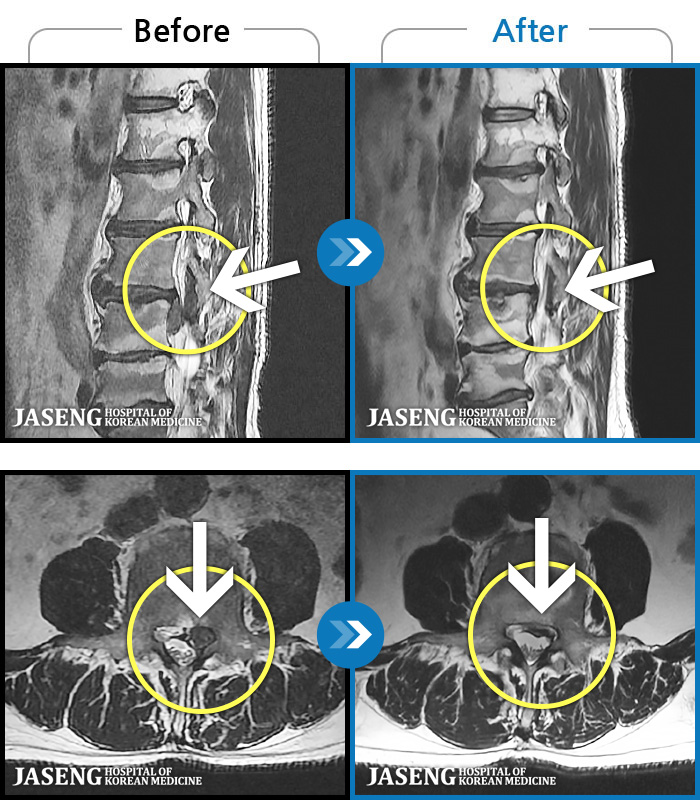

[뱸] 19.11.28~25.05.06